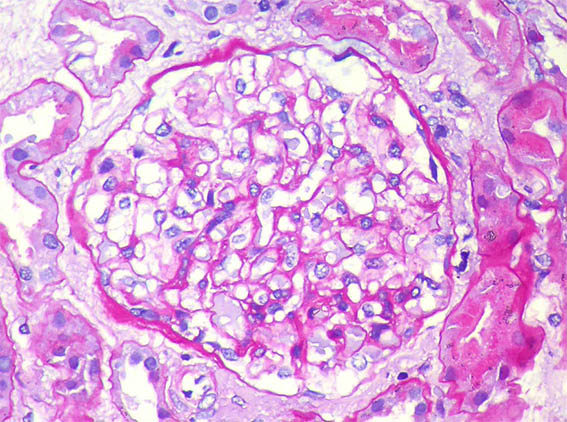

Figure 4. PAS, X400.